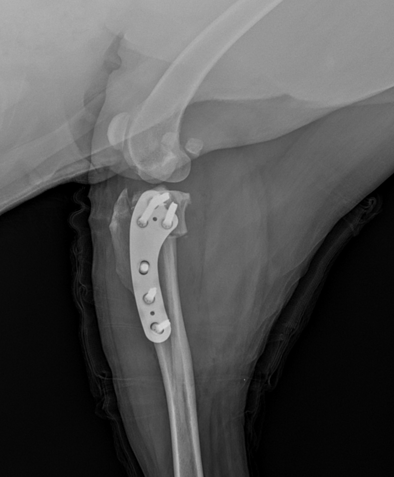

TPLO

TPLO Tibial Plateau Leveling Osteotomy

전십자인대 단열에서 가장 널리 이용되는 뼈자름술로 무릎관절의 경사를 완만하게 만들어주어 정강이뼈가 앞으로 밀리게 되는 증상을 방지하는 수술법으로 높은 치료 성공률을 보입니다.

• 십자인대 수술 이미지

TPLO 십자인대 수술

절뚝거리는 증상으로 내원!

TPLO 수술 후 건강한 일상으로 복귀